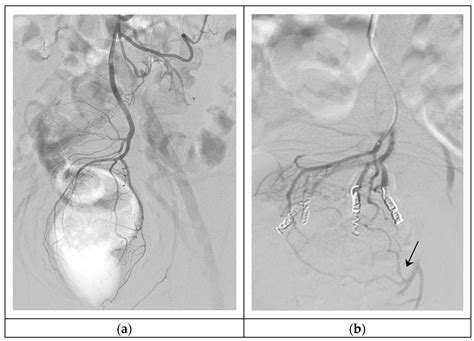

Hemorrhoid Artery Embolization is a cutting-edge, image-guided procedure performed by interventional radiologists. Unlike traditional surgery, which physically removes the hemorrhoidal tissue, HAE works by targeting the blood supply that feeds the hemorrhoids. By reducing the arterial blood flow to the hemorrhoidal plexus, the procedure causes the hemorrhoids to shrink over time, effectively alleviating symptoms like bleeding, pain, and protrusion.

Because it is a minimally invasive technique, it does not require general anesthesia or incisions in the sensitive anal region. Instead, a tiny catheter is guided through a blood vessel in the wrist or groin to the specific arteries supplying the hemorrhoids. Small particles are then injected to block these vessels, successfully reducing the pressure and engorgement of the hemorrhoidal tissues.

3. Embolization: Once the specific hemorrhoidal arteries are identified, specialized embolic agents are injected to reduce the blood supply.

Clinical studies have consistently demonstrated that Hemorrhoid Artery Embolization is highly effective in controlling symptoms, particularly rectal bleeding. Most patients notice a significant improvement within a few weeks as the hemorrhoidal tissue gradually shrinks. Because the blood supply is permanently reduced, the recurrence rate is low, provided that patients maintain a lifestyle that prevents chronic constipation and straining.